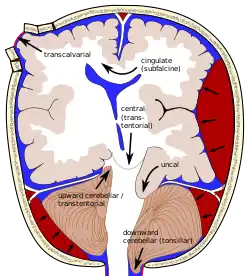

The tentorium is an extension of the dura mater that separates the cerebellum from the cerebrum. There are two major classes of herniation: supratentorial and infratentorial. Supratentorial refers to herniation of structures normally found above the tentorial notch, and infratentorial refers to structures normally found below it.[7]

- Supratentorial herniation

1) Uncal (transtentorial)

2) Central

3) Cingulate (subfalcine or transfalcine)

5) Tectal (posterior)

- Infratentorial herniation

6) Upward (upward cerebellar or upward transtentorial)

7) Tonsillar (downward cerebellar)